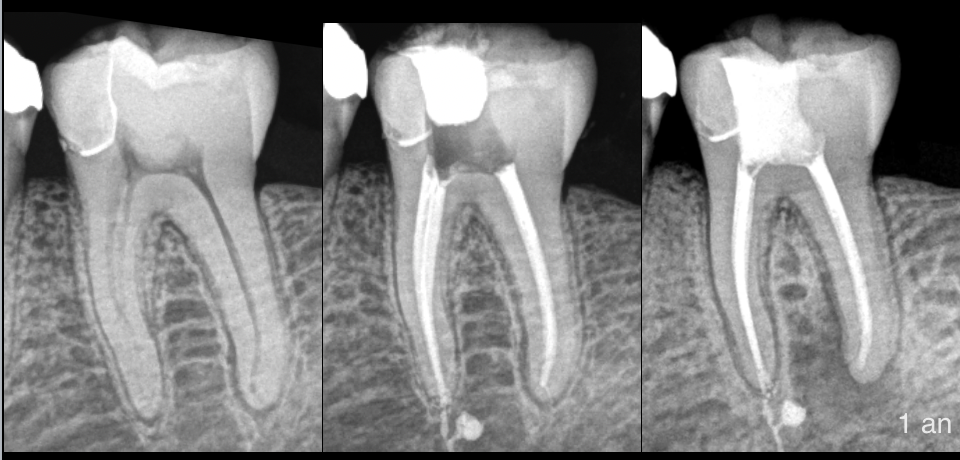

🔬 Le contrôle à 1 an met en évidence un traitement qui n’est pas suffisamment efficace du point de vue de l’environnement osseux en distal.

⚠️ Le patient était prévenu dès la consultation du pronostic de 90%.

💉 Indication de complément de désinfection par microchirurgie endodontique.